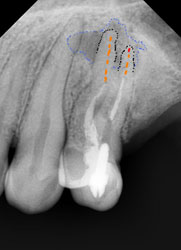

На этом рентгеновском снимке видны, в первую очередь, «пустые» корневые каналы и довольно больших размеров очаг воспаления (то, что часто называют гранулемой, кистой) на верхушке одного из корней. В общем итоге в одном зубе был сконцентрирован целый букет ошибок и недоделок, одним словом, это образец недобросовестной работы стоматолога. Я стараюсь о коллегах всегда говорить или хорошо или молчать, но в данном случае надо смотреть правде в глаза – зуб загублен именно стоматологом. Никаких объективных сложностей для качественной работы изначально здесь не было. Зато появились теперь. Прогноз на будущее для таких зубов всегда строится, исходя из 2 основных проблем – насколько приведет к успеху повторное лечение каналов и насколько будет успешной попытка адекватного восстановления зуба после этого. Оценив вероятность долговременного успеха этих двух составляющих, можно решать, стоит ли «спасать» зуб от щипцов хирурга. Ведь, в любом случае, лечение стоит денег, а гарантировать результат здесь невозможно. Можно только предполагать вероятность успеха. В данном случае каналы не выглядели непроходимыми. Да и восстановить зуб коронкой, даже несмотря на большую степень разрушения, все еще представлялось возможным. А потому было принято решение о начале лечения.